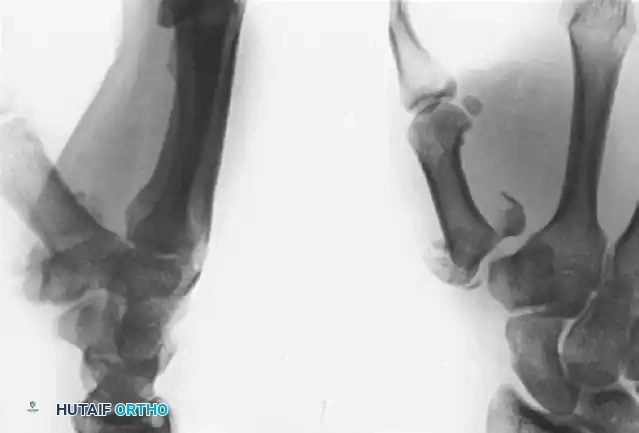

Introduction to Thumb Metacarpal Base Fractures

Fractures of the base of the thumb metacarpal represent a unique and challenging subset of hand trauma. The trapeziometacarpal (TMC) joint is a highly mobile, biconcave saddle joint that is fundamental to the biomechanics of pinch and grasp. Disruption of this articular surface, as seen in Bennett (two-part) and Rolando (three-part or comminuted) fractures, rapidly leads to post-traumatic osteoarthritis and profound functional impairment if not anatomically restored.

Understanding the deforming forces acting upon the thumb metacarpal is critical for achieving and maintaining reduction. The fracture patterns are dictated by the intrinsic and extrinsic musculotendinous units crossing the first carpometacarpal (CMC) joint.

• The Volar Ulnar Beak Fragment: In both Bennett and Rolando fractures, the volar ulnar articular fragment remains anatomically reduced within the TMC joint. It is held securely in place by the robust anterior oblique ligament (AOL), which originates from the trapezium.

• The Metacarpal Shaft: The distal metacarpal shaft is subjected to powerful deforming forces. The abductor pollicis longus (APL) inserts at the dorsal-radial base of the metacarpal, pulling the shaft proximally, dorsally, and radially. Simultaneously, the adductor pollicis pulls the distal aspect of the metacarpal ulnarly into the palm, creating a supination and adduction deformity.

The hallmark of a thumb metacarpal base fracture is the proximal, dorsal, and radial subluxation of the metacarpal shaft driven by the APL. Successful ORIF requires counteracting these exact vectors during the reduction maneuver: longitudinal traction, palmar abduction, and pronation.